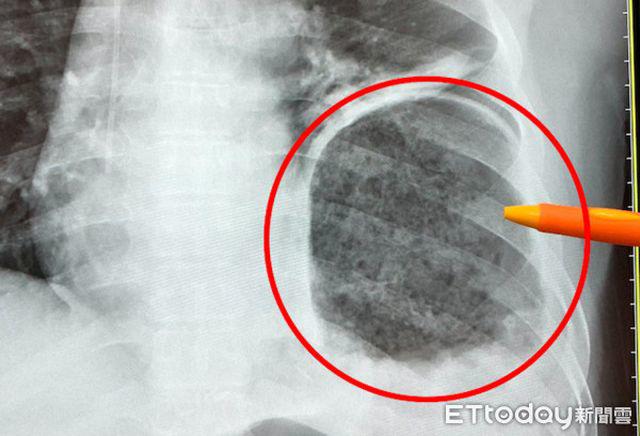

Ông Lý, 45 tuổi bị ung thư trực tràng, sau phẫu thuật, hóa trị liệu, ông Lý đã được về nhà dưỡng sức, nhưng còn một vấn đề là đi đại tiện không thuận lợi, thường bị táo bón. Vào một ngày, ông Lý ở trong nhà vệ sinh dùng lực đi đại tiện, phần bụng trên đột nhiên cảm thấy đau dữ dội, nhưng vì cơn đau không kéo dài nên ông cũng không để ý. Đến 1 tháng sau, ông Lý trở lại phòng khám, bác sĩ kiểm tra phát hiện dạ dày "chạy" lên ngực, vỡ cơ hoành, phổi phía bên trái bị dạ dày chèn ép một nửa.

Bắc sĩ Ngô Chính Nguyên, Trưởng Khoa phẫu thuật lồng ngực của Bệnh viện Từ Tế Đài Trung cho biết, khi đó ông Lý quay lại phòng khám, bác sĩ Khoa đại trực tràng phát hiện có điều không ổn, vội vàng chuyển ông Lý đến khoa Phẫu thuật lồng ngực, sau khi kiểm tra chụp cắt lớp CT mới phát hiện ra vấn đề này. Hình ảnh chụp cắt lớp cho thấy dạ dày bị sưng và đầy thức ăn, phối bên trái bị dạ dày ép một nửa, may mắn thay, phổi không có vì bị ép mà dẫn đến khó thở, nhưng nếu phổi lại bị kéo xuống, có thể dẫn đến xoắn dạ dày, hoại tử do thiếu máu, nghiêm trọng hơn là mất mạng.

Bác sĩ Ngô Chính Nguyên đánh giá rằng, ông Lý đã trải qua phẫu thuật trực tràng và hóa trị liệu, đường ruột dễ bị đầy hơi. Do đó, dùng lực khi đi đại tiện khiến cho áp lực ổ bụng cao hơn so với người bình thường. Khi đó có một cơn đau dữ dội, đó là cơ hoành tạo ra một lỗ hổng. Nhưng sau đó ông Lý không chú ý, trong vòng 1 tháng vẫn có thói quen dùng lực đi đại tiện khiến dạ dày bị dọc theo cơ hoành bị vỡ lên phổi. Sau một thời gian dài, lỗ nhỏ ban đầu mở rộng thành 7 cm, dạ dày chèn ép vào ngực trái, khiến cơ hoành bị sa xuống.